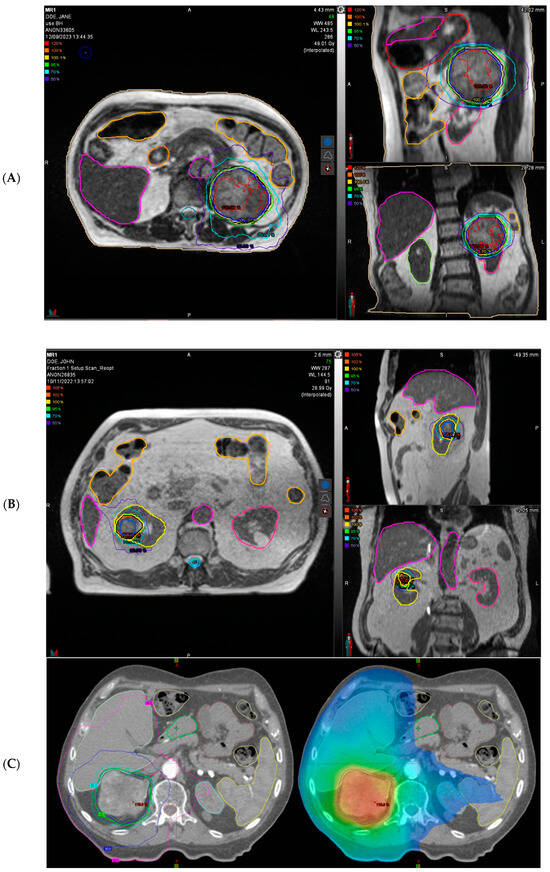

- Tetar, S.U.; Bohoudi, O.; Senan, S.; Palacios, M.A.; Oei, S.S.; van der Wel, A.M.; Slotman, B.J.; van Moorselaar, R.J.A.; Lagerwaard, F.J.; Bruynzeel, A.M.E. The Role of daily adaptive stereotactic MR-guided radiotherapy for renal cell cancer. Cancers 2020, 12, 2763. [Google Scholar] [CrossRef]

- Yim, K.; Hsu, S.-H.; Nolazco, J.I.; Cagney, D.; Mak, R.H.; D’Andrea, V.; Singer, L.; Williams, C.; Huynh, E.; Han, Z.; et al. Stereotactic Magnetic Resonance–guided Adaptive Radiation Therapy for Localized Kidney Cancer: Early Outcomes from a Prospective Phase 1 Trial and Supplemental Cohort. Eur. Urol. Oncol. 2024, 7, 147–150. [Google Scholar] [CrossRef] [PubMed]